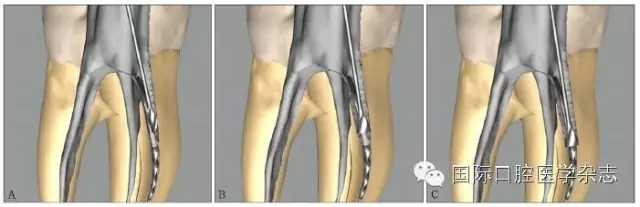

3.2.1 牙本質(zhì)厚度評(píng)估 取出分離器械需要損失部分牙本質(zhì),牙本質(zhì)的損失量包括縱向損失和橫向損失。縱向損失決定于取出時(shí)分離器械冠方末端需要暴露的長度,橫向損失決定于分離器械的斷端直徑以及選用取出器械的方法(如超聲法或是環(huán)鉆法等)。牙本質(zhì)損失量過多會(huì)導(dǎo)致根管穿孔、根管折斷等并發(fā)癥[7](圖3)。

A:紅色及綠色的部分分別表示用改良GG鉆及超聲工作尖去除牙本質(zhì)的量;B:MicroCT掃描圖像顯示取出下頜第一磨牙近頰根管中分離器械后,導(dǎo)致了根管穿孔。

圖 3 取分離器械過程中會(huì)導(dǎo)致牙本質(zhì)損失,甚至穿孔等并發(fā)癥

取出分離器械后,根管壁的殘余牙本質(zhì)厚度是影響牙根抵抗力的重要因素,因而,可以認(rèn)為殘余牙本質(zhì)的厚度是影響分離器械取出與否的最重要的因素之一[8]。